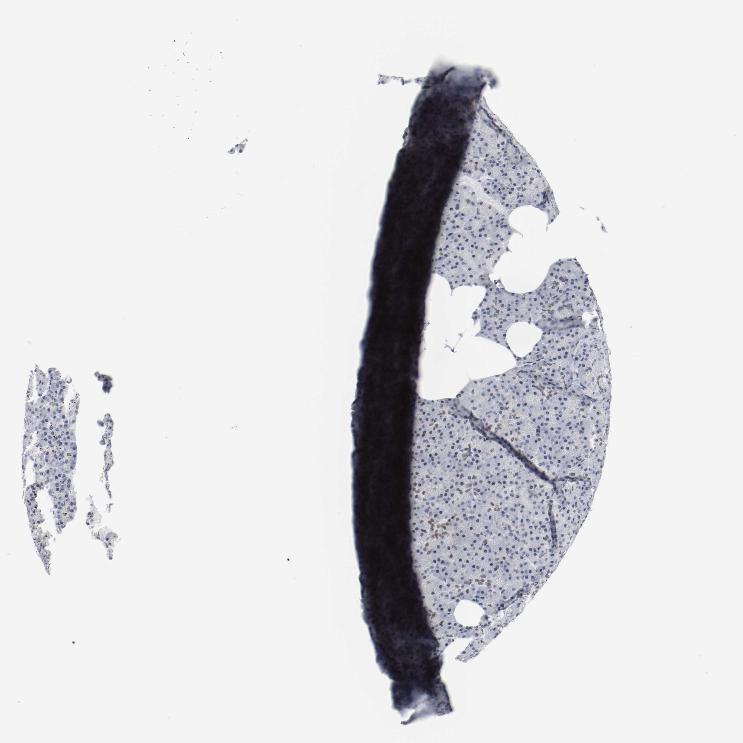

PANCREAS - Antibody stainingi

Antibody staining in the annotated cell types in the current human tissue is reported as not detected, low, medium, or high, based on conventional immunohistochemistry profiling in selected tissues. This score is based on the combination of the staining intensity and fraction of stained cells.

Each image is clickable and will lead to virtual microscopy that enables deeper exploration of all samples and also displays staining intensity scores, fraction scores and subcellular localization as well as patient and tissue information for each sample.

Antibody HPA001759Antibody CAB004318

Exocrine glandular cells MediumLow

Pancreatic endocrine cells Medium-